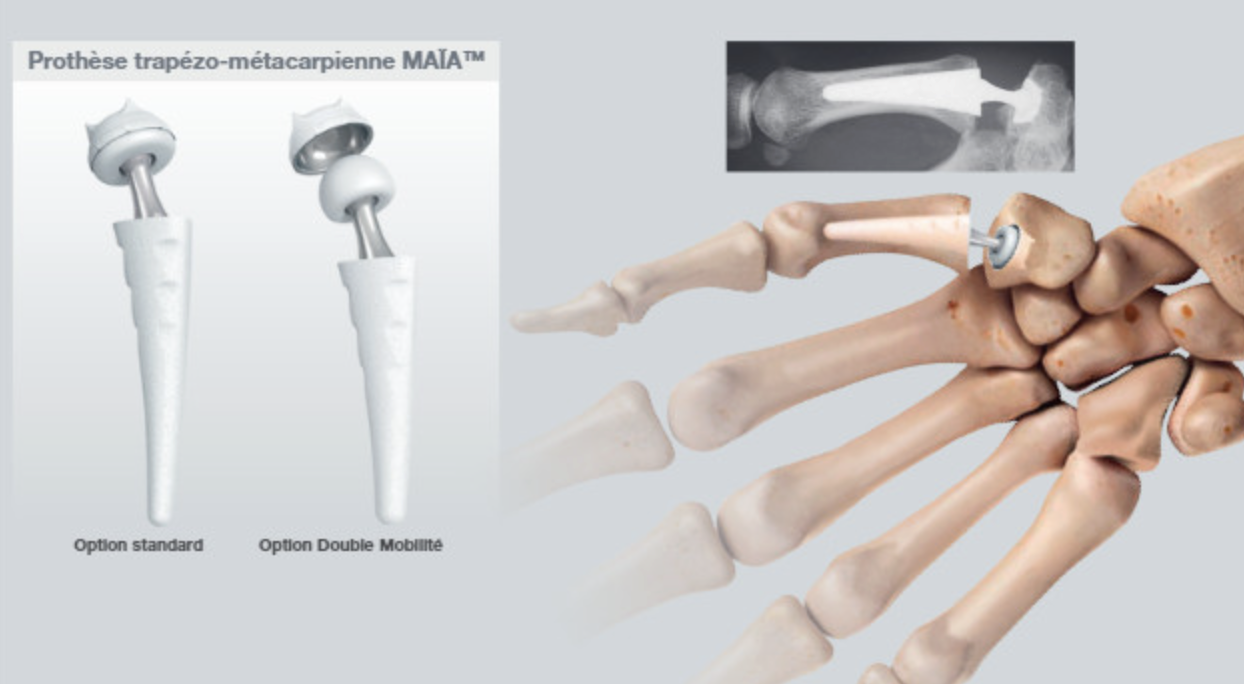

- Prothèse trapézo-métacarpienne : Il est possible de poser une prothèse pour remplacer l’articulation, à l’instar de la prothèse de hanche. Cela permet de maintenir la mobilité tout en supprimant la douleur, et de retrouver la force.